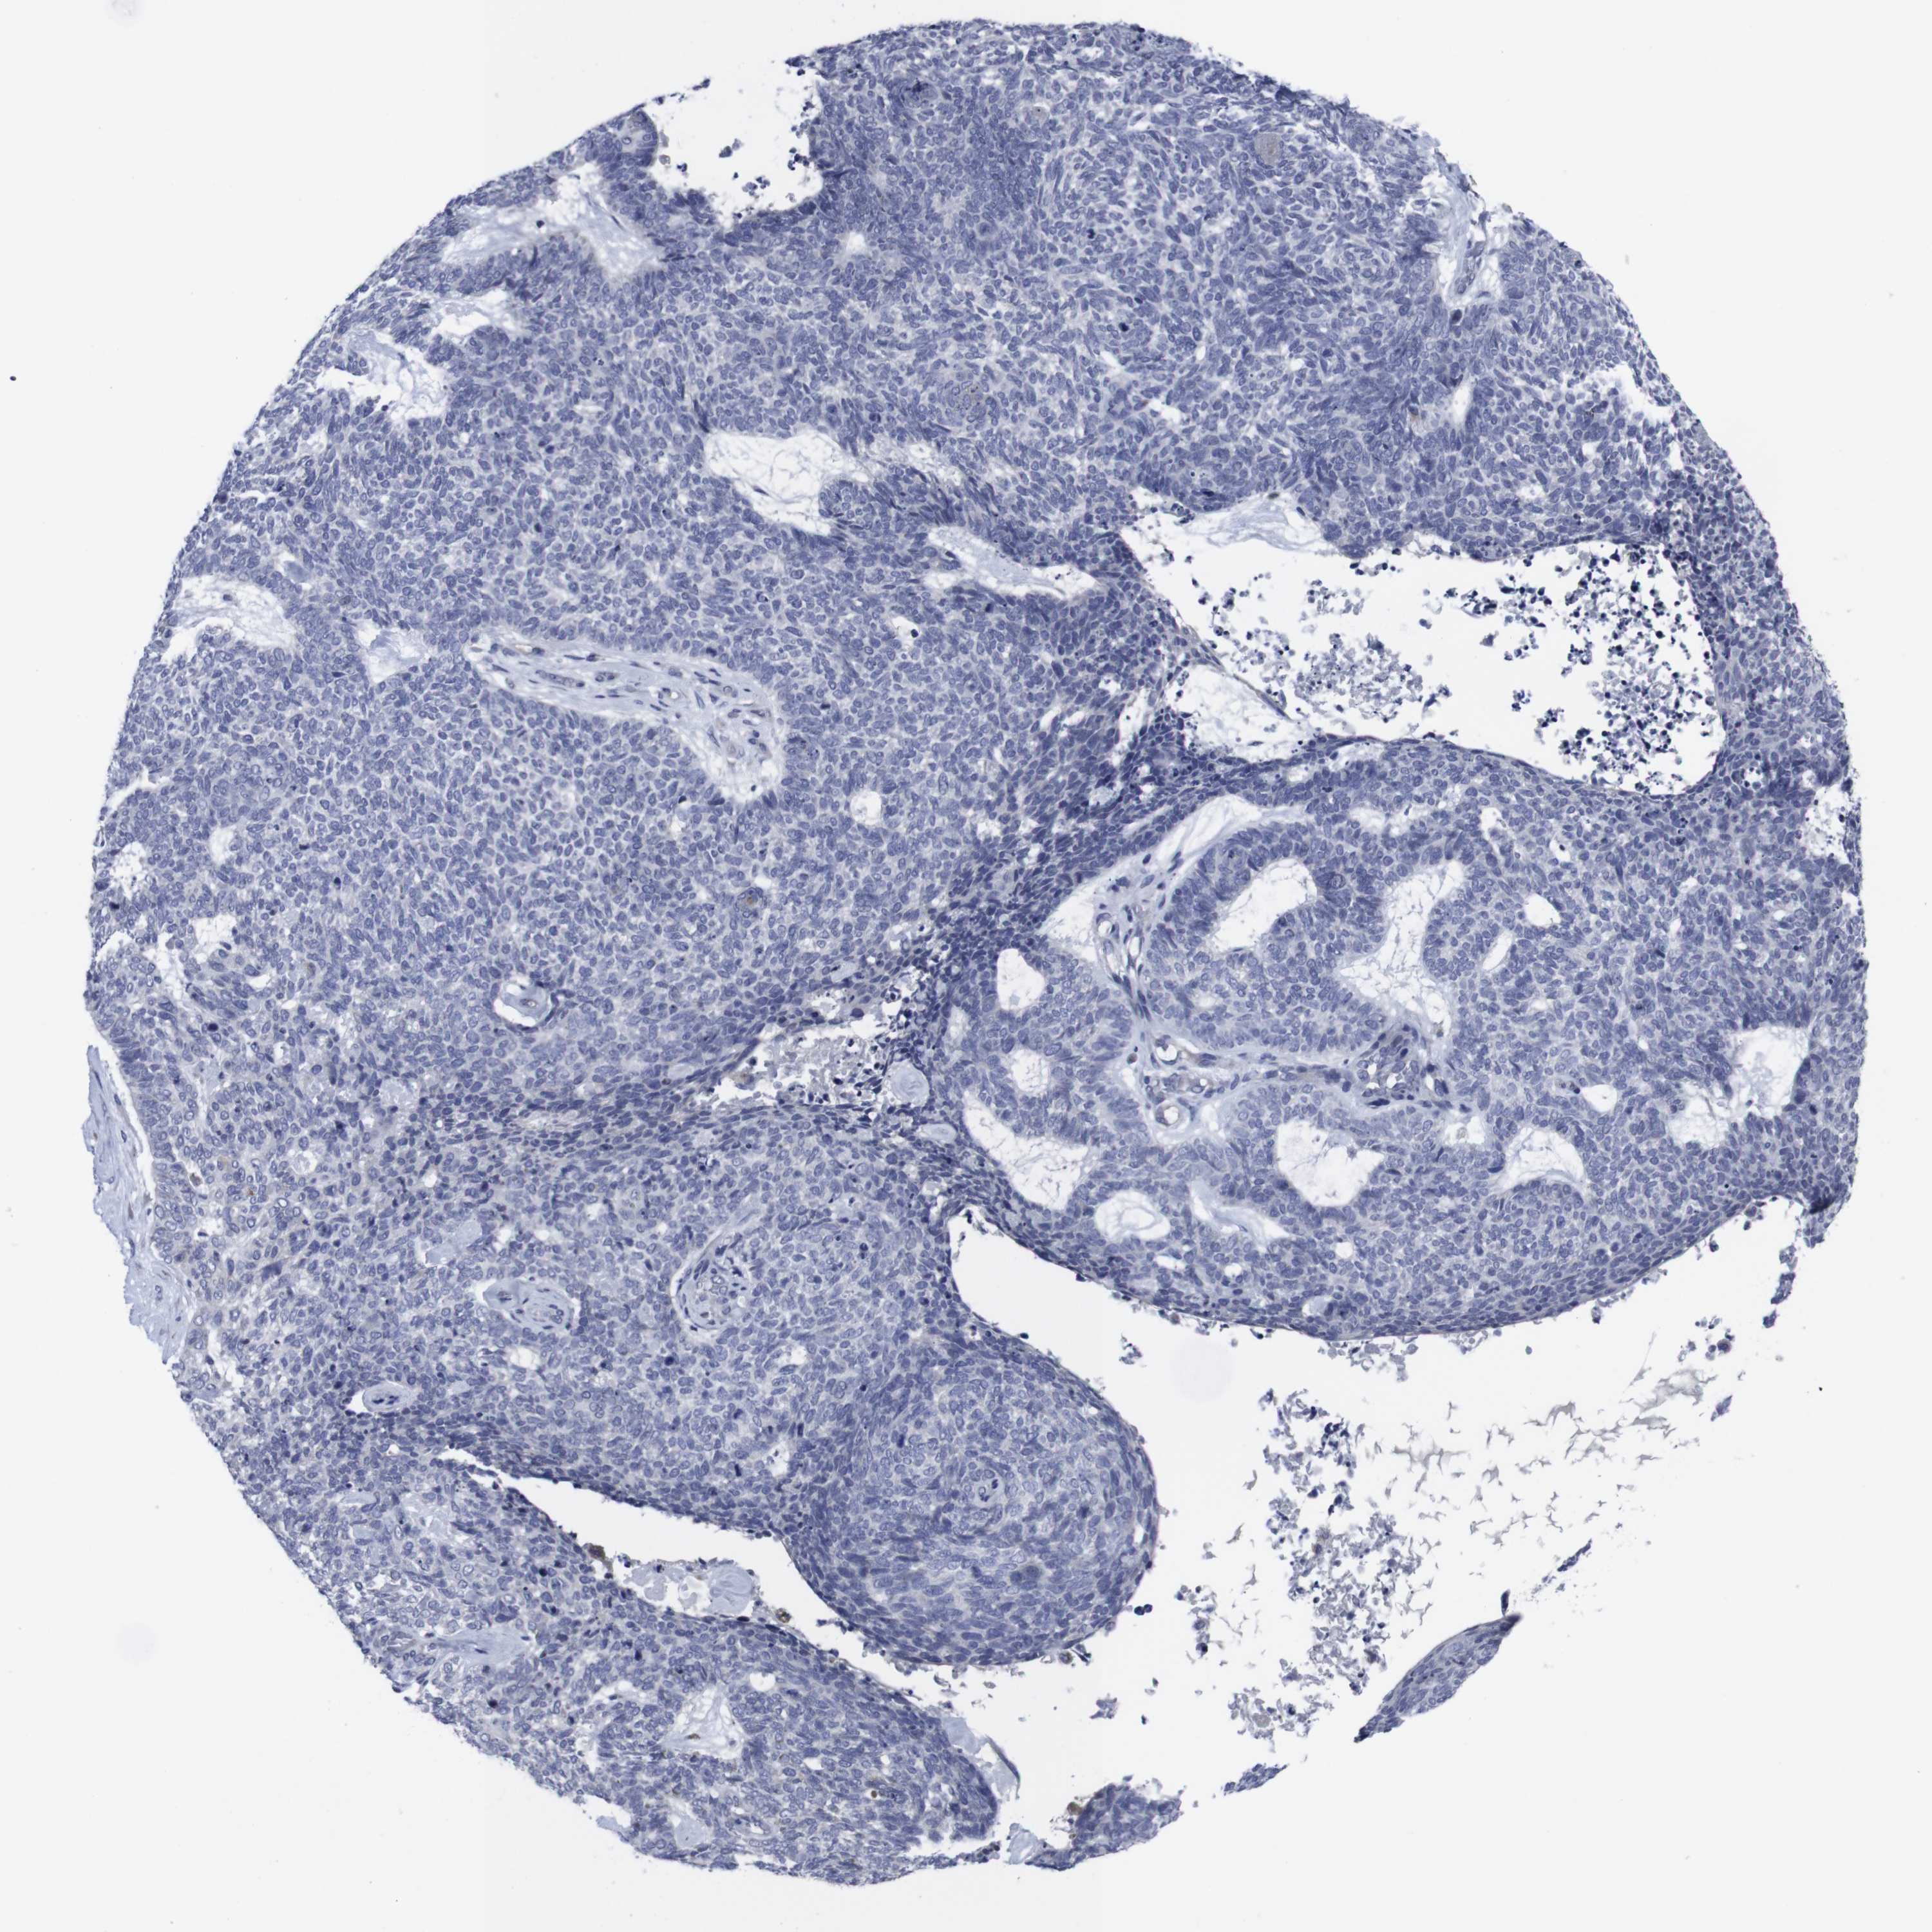

SKIN CANCER - Protein expressioni

A mouse-over function shows sample information and annotation data. Click on an image to view it in a full screen mode. Samples can be filtered based on level of antibody staining by selecting one or several of the following categories: high, medium, low and not detected. The assay and annotation is described here.

Each image is clickable and will lead to virtual microscopy that enables deeper exploration of all samples and also displays staining intensity scores, fraction scores and subcellular localization as well as patient and tissue information for each sample.

Antibody CAB001452

Staining

Low

Intensity

Weak

Quantity

<25%

Location

None

Basal cell carcinoma